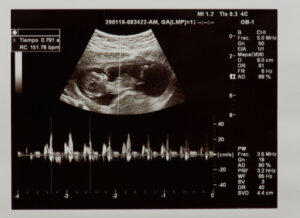

By heartbeat, we’re referring to the number of times the heart contracts during one minute. The fetal heart rate is identifiable in the first weeks of gestation by means of an ultrasound or a monitor known as fetal Doppler.

First, the ultrasound technician will assess whether the heartbeat is actually present, thus checking fetal vitality. In addition, they’ll evaluate how many times the heart beats during one minute. The values considered normal in the fetal stage are between 120 and 160 beats per minute.

Assessment of the anatomy and physiology of the baby’s heart can be performed in the mother’s womb. This is thanks to the ultrasounds performed during prenatal check-ups, which make it possible to assess, among other parameters, cardiac health, and the fetal heartbeat.

Certainly, during the second trimester, morphological ultrasound is indicated, where the baby’s organs are studied in detail. Here, the cardiac structures of the fetus, such as the chambers, valves, and blood vessels of the heart, are carefully observed.

It also evaluates the functioning of the heart and whether there are any problems in its mechanism or conduction. Morphological ultrasound also diagnoses the existence of congenital heart disease that may cause problems after the baby is born.